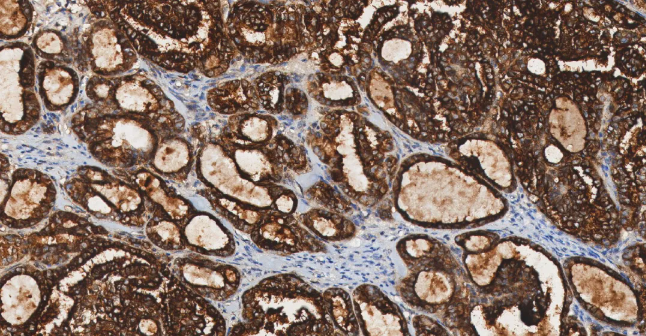

图 9. 结直肠癌患者 CDX2 免疫染色结果。

CDX2 在结直肠癌中普遍表达,是确诊肠源性肿瘤的首选标志物。CDX2 具有诊断和预后两方面的意义。一方面它有助于鉴别原发灶不明的转移癌,另一方面在结直肠癌中,其表达状态与分子亚型和预后相关。

CDX2

• 功能:CDX2 是肠上皮细胞分化和功能维持的关键转录因子,调控众多肠道特异性基因的表达。